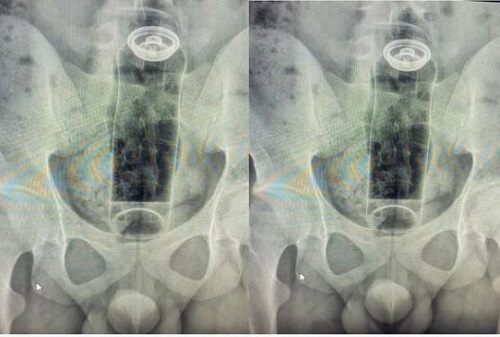

Um jovem de 19 anos precisou ser hospitalizado após um objeto ficar preso no reto durante uma prática sexual. O caso, atendido pelo cirurgião coloproctologista Daniel Brosco, envolveu a introdução de um desodorante no ânus, que acabou sendo sugado pelo intestino e não pôde ser retirado em casa.

Segundo o médico, o paciente relatou que usava o objeto durante uma “brincadeira” sexual quando a embalagem subiu para o reto, exigindo internação para a retirada. O episódio levou o especialista a fazer um alerta público nas redes sociais sobre os riscos do uso de itens inadequados para esse tipo de prática.